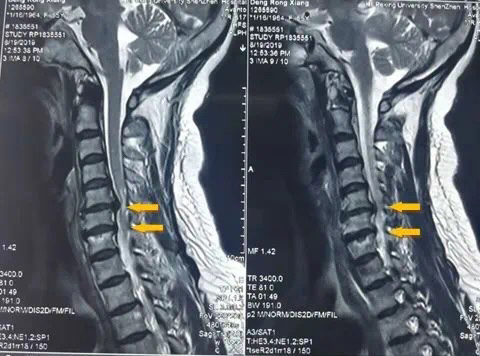

在颈椎病人中会出现各类症状表现,每一种表现都具有特定的临床体征,故此临床上分为颈型、神经根型、椎动脉型、交感神经型、混合型与脊髓型。颈椎的结构较为 复杂,在骨骼各部分组合中,血管、神经等组织又潜入它的边缘与结构中。因此骨骼关节的病理变化必然波及到这些组织,使其受到刺激与压迫,出现病人所感觉的

症状与医生所查的临床体征表现。对颈椎病病理变化的认识,必须从颈椎骨骼、关节结构、椎间盘组织进行查源分析。